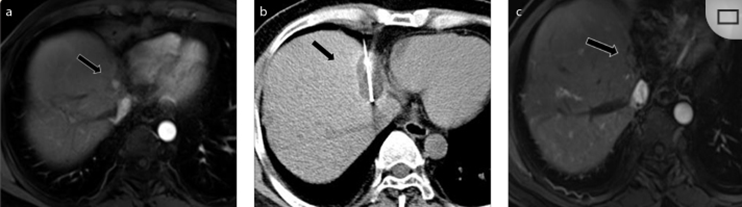

( a ) 軸向 MRI 和 ( b ) 軸向 CT 顯示肝S8段有一個(gè)16mm的病灶,鄰近肝緣。( c )冷凍消融期間CT顯示放置了2個(gè)冷凍探針,低密度冰球包圍病灶。(d)術(shù)后1個(gè)月隨訪 CT顯示冰球?qū)?yīng)的壞死區(qū)域,未見復(fù)發(fā)。(e)術(shù)后6個(gè)月的CT,壞死區(qū)域縮小,未見復(fù)發(fā)。(f)與基線影像(g)相比,12個(gè)月后的FDG-PET/CT顯示未見FDG攝取。

62歲女性,肝轉(zhuǎn)移(卵巢癌)腫瘤的完全消融病例(a)軸向CT顯示病變位置毗鄰心臟和上腔靜脈(黑色箭頭)。(b)術(shù)中軸向CT掃描:使用三個(gè)冷凍探針。1個(gè)月后的軸向(e)和冠狀位(f)增強(qiáng)CT掃描顯示低密度區(qū)域,由于肉芽組織反應(yīng)引起的邊緣增強(qiáng)。